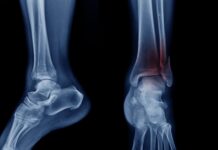

D’altronde, l’allineamento è il momento più delicato di tutto l’intervento: per questo nel tempo sono state ideate tecnologie capaci di facilitare il compito del chirurgo e garantire un allineamento perfetto della protesi con tibia e femore. Ultimamente ci si è spinti oltre, con l’immissione sul mercato di robot che possono assistere il chirurgo nelle varie fasi dell’intervento, partendo da quelle di simulazione preoperatoria.

Sperimentato dall’équipe del dott. Danilo Francesco Chirillo, direttore dell’Ortopedia del Santo Spirito, il robot permette di personalizzare al massimo non solo la scelta della protesi, ma anche la procedura chirurgica, in particolare nella rimozione della cartilagine e dell’osso usurato, nei tagli a livello di femore e tibia e nell’inserimento delle componenti protesiche. Anche l’allineamento ne trae giovamento.

Si applicano a gamba e coscia del paziente di sensori appositi che permettono la navigazione robotica, oltre a un altro strumento che garantisce la ricostruzione 3D di quanto sta avvenendo. Grazie a questi dispositivi, il chirurgo può effettuare uno studio del movimento in flessione ed estensione del ginocchio, misurando la tensione dei legamenti. I risultati così ottenuti, unisti a quelli della ricostruzione 3D, permettono di posizionare le componenti protesiche con un margine di errore inferiore a 1° e a 1 mm. Il tutto partendo da un’incisione operatorio standard.